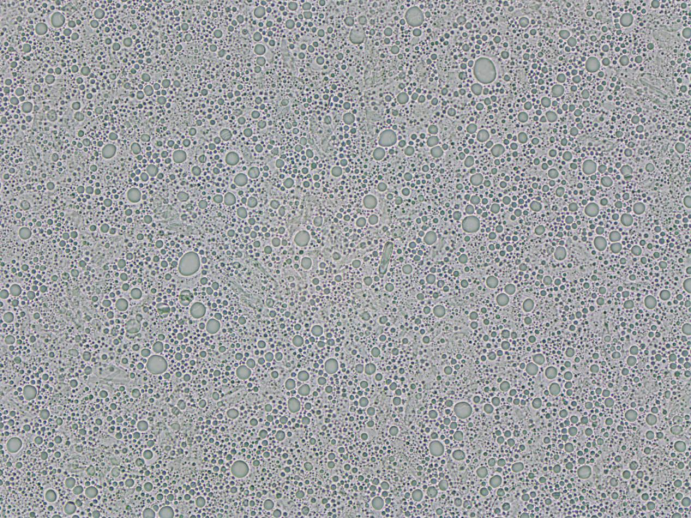

通過 ZML310 儀器的全面檢測,夫西地酸乳膏的顆粒特性(含方晶析出情況)被精準量化,核心數(shù)據(jù)與分析如下:

粒徑分布:方晶析出無異常大顆粒,符合質(zhì)量標準

粒徑分布是判斷方晶析出是否影響制劑質(zhì)量的核心指標。本次測試結(jié)果顯示,樣品顆粒粒徑呈現(xiàn)集中分布、無異常峰值。

關(guān)鍵參數(shù)粒徑:

a.D10=2.90μm(10% 顆粒粒徑小于該值,反映小顆粒占比)

b.D50=5.26μm(中位粒徑,代表顆粒整體大小水平)

c.D90=8.32μm(90% 顆粒粒徑小于該值,反映大顆粒上限)

d.D99=11.41μm(99% 顆粒粒徑小于該值,無超標的大尺寸方晶)。

分段粒徑百分含量:

a.0.0-10.0μm 區(qū)間占比97.52%

b.0.0-5.0μm 區(qū)間占比 44.68%

c.2.0-4.0μm 區(qū)間占比 23.00%

d.而 54.5μm 以上區(qū)間顆粒占比均為 0.00%,表明樣品中未出現(xiàn)可能引發(fā)皮膚刺激的大尺寸方晶析出。

分布均勻性:

a.體積平均粒徑為 5.42μm

b.顆粒平均粒徑為 4.52μm

c.離散系數(shù)為 37.90%,

d.標準偏差為 2.05μm,說明顆粒大小分布相對均勻,無明顯團聚形成的 “偽大顆粒”,間接反映乳膏制備工藝中分散步驟控制良好,方晶析出處于可控范圍。